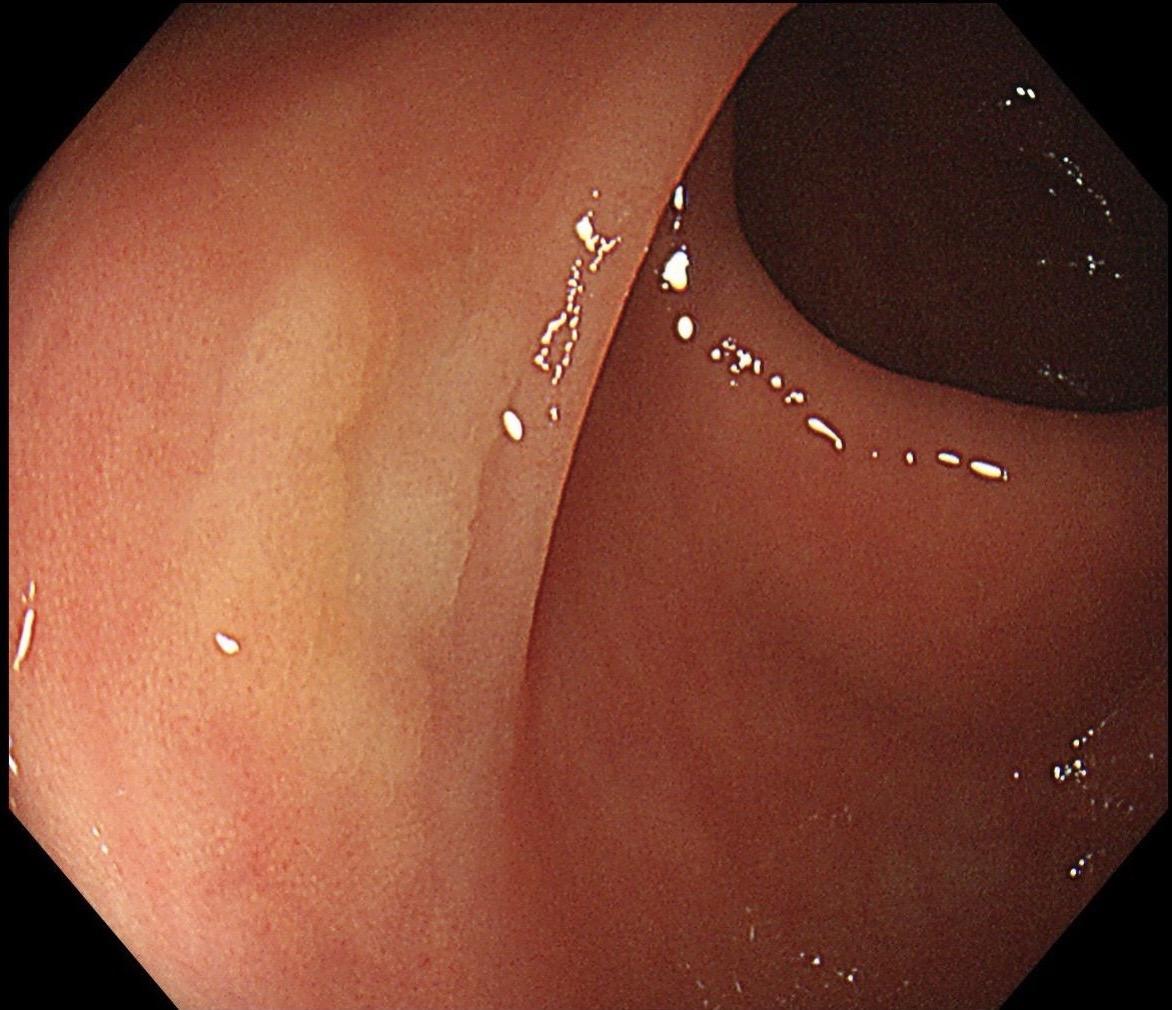

结肠SSL 醋酸染色。染色效果不亚于靛胭脂,结合NBI,Near focus观察表面结构非常OK,下次让护士长买大桶装的,1桶6块9,可以喷一年,哈哈……

结肠SSL 醋酸染色。染色效果不亚于靛胭脂,结合NBI,Near fo...